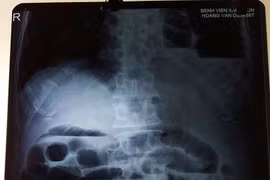

Ho, khó thở tưởng hậu Covid-19, nam thanh niên 25 tuổi cố chịu đựng điều trị tại nhà. Khi ho và tức ngực không chịu được bệnh nhân mới đi khám mới hay thoát vị hoành trái do vỡ cơ hoành.